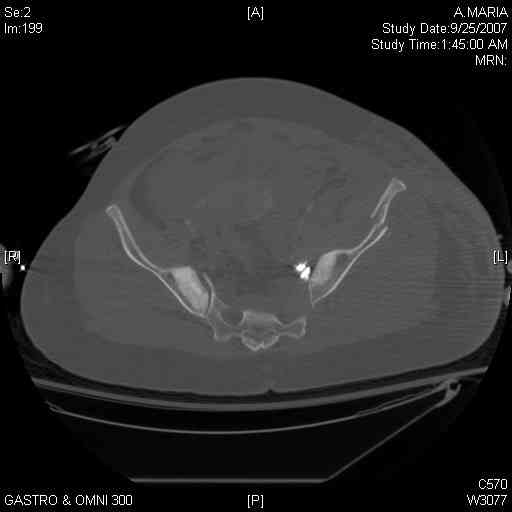

It's a comminuted iliac fracture involving the GS notch and all that

implies...use the lateral interval of an ilioinguinal, sequentially reduce,

and fix...if you want to, you can attach the dominant unstable fragment to

both the stable posterior iliac fragment and also to the anterolateral portion of the sacrum using plates...if you choose to anchor to both, the implants get congested on the iliac side of the SI joint so be precise with contouring and such applications...perhaps and based on the images shown, an iliosacral screw would only augment the construct if applied to the second sacral segment (but this is difficult to assess on the images shown). The crest components can be held securely with screws and/or peripheral plating.

Thanks. I probably didn't include enough images on the CT, but it didn't look to me like an SI screw would be of value except into S2, which I am not

comfortable placing. I will post finals if the neurosurgeons let me operate on her. ICPs still a problem.

I always manage these percutaneously. The basic idea is to peg the AIIS fragment to the crescent frag still attached to the sacrum.

But the reported results of open treatment are very good, so your plan of ORIF should yield acceptable results.